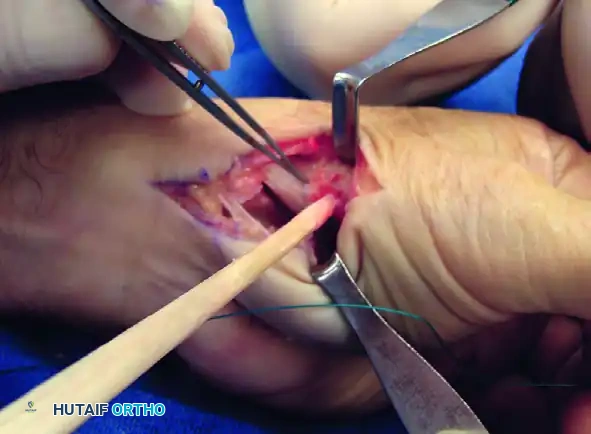

Figure: Gouge tract created in the sagittal diameter of the metacarpal, emerging at its volar beak. A small branch of the radial nerve is retracted volarly.

Intraoperative view demonstrating the creation of the metacarpal tunnel.

Intraoperative view of the FCR tendon strip harvested and prepared for routing.

Intraoperative view showing the tendon strip being pulled dorsally through the metacarpal tunnel.